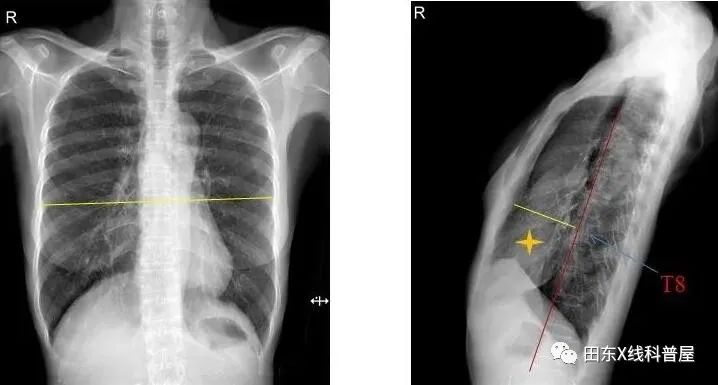

胸椎曲度弧高(左侧位胸片测量):T4-T12做一连线,测T8椎体前缘与该直线的垂直距离,其距离若<12mm,可考虑SBS。

测量胸廓前后径/横径比值≤0.33。

具体出来:胸椎曲度孤高<12mm,胸廓前后径/横径比值≤0.33。